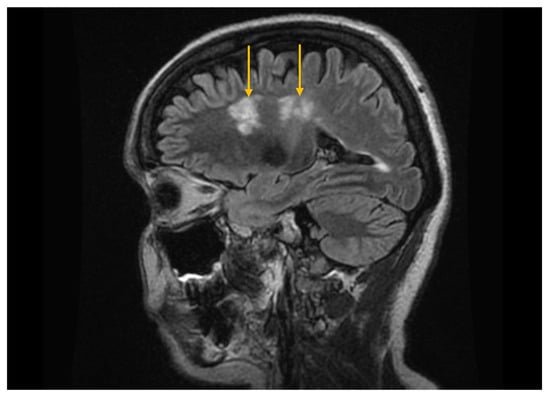

The Role of Imaging Techniques in the Evaluation of Extraglandular Manifestations in Patients with Sjögren’s Syndrome

Sjögren’s syndrome is a chronic autoimmune disease marked by lymphocytic infiltration of the exocrine glands and the development of sicca symptoms, yet some patients also develop extraglandular involvement. Imaging has become relevant for describing these systemic features and supporting clinical assessment. This review discusses the roles of ultrasonography, elastography, computed tomography, and magnetic resonance imaging in evaluating multisystem disease associated with Sjögren’s syndrome. Ultrasonography and elastography help assess muscular involvement by showing changes in echogenicity and stiffness that reflect inflammation and later tissue remodeling. In joints, ultrasound can detect synovitis, tenosynovitis, and early erosive changes, including abnormalities not yet evident on examination. Pulmonary disease, most often with interstitial lung involvement, is best evaluated with high-resolution computed tomography, which remains the most reliable imaging modality for distinguishing interstitial patterns. Magnetic resonance imaging is valuable in assessing neurological complications. It can reveal ischemic and demyelinating lesions, neuromyelitis optica spectrum features, or pseudotumoral appearances. Imaging is also essential for detecting lymphoproliferative complications, for which ultrasound and magnetic resonance imaging can reveal characteristic structural and diffusion-weighted imaging findings. When combined with clinical and laboratory information, these imaging methods improve early recognition of systemic involvement and support accurate monitoring of disease progression in Sjögren’s syndrome. Full article